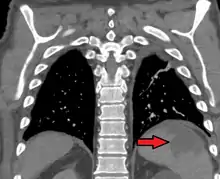

Splenic infarction

Splenic infarct seen on CT

Splenic infarction is a condition in which blood flow supply to the spleen is compromised,[1] leading to partial or complete infarction (tissue death due to oxygen shortage) in the organ.[2] Splenic infarction occurs when the splenic artery or one of its branches are occluded, for example by a blood clot.[3]

An abdominal CT scan is the most commonly used modality to confirm the diagnosis,[3] although abdominal ultrasound can also contribute.[5][6][7]